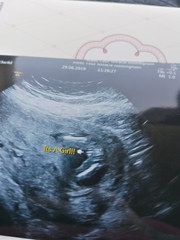

Hi everyone I am new to this thread our lo is due 12 of December I had a private scan today at 15w 4 days it took ages for the baby to move as the cord was their and legs crossed she gave us a potty shot but I still think I saw something else could be wrong what dose everyone think could it be too early today its a girl